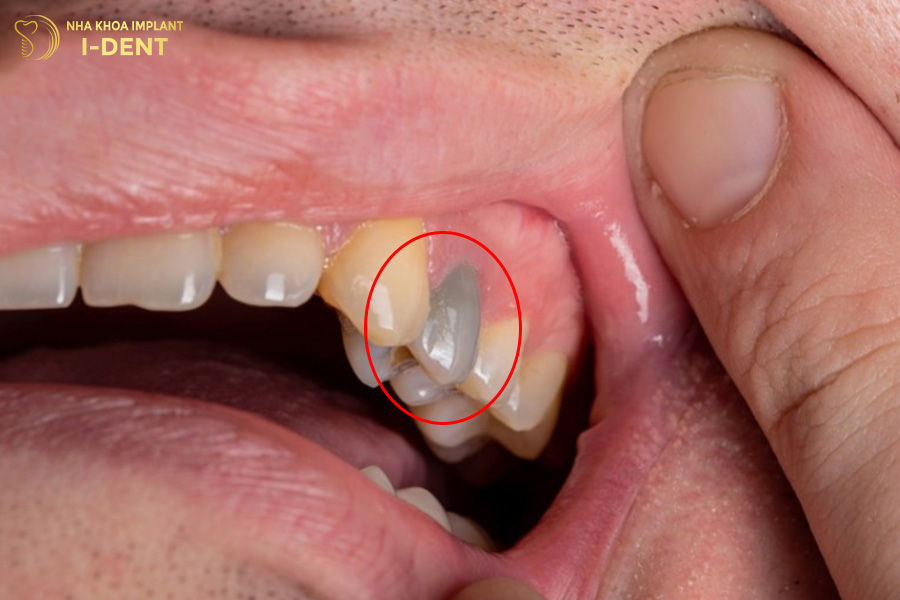

1.9. Viêm tủy hoặc chết tủy răng

Một hậu quả nghiêm trọng khác mà niềng răng có thể gây ra là viêm tủy hoặc chết tủy răng. Khi lực chỉnh nha quá mạnh hoặc kéo dài, hệ thống mạch máu nuôi tủy có thể bị chèn ép, dẫn đến thiếu máu và hoại tử tủy. Người bệnh thường cảm thấy đau nhức dữ dội, răng trở nên nhạy cảm với nhiệt độ và có thể đổi màu theo thời gian. Khi tủy đã chết, việc điều trị nội nha là bắt buộc để bảo tồn răng, làm gián đoạn quá trình niềng.

Niềng răng có thể làm chết tủy răng nếu thực hiện sai kỹ thuật.